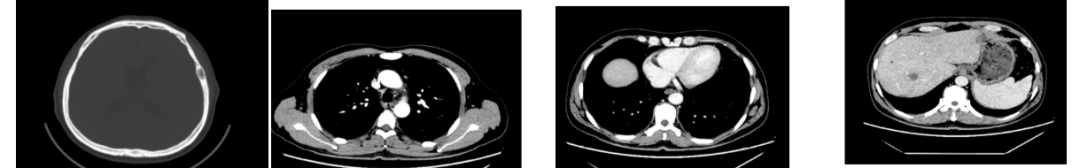

外院CT检查提示:1、两肺多发斑片状、结节影,性质待定,转移瘤?2、纵隔内多发肿大淋巴结;3、肝实质多发稍低密度影,性质待定(转移瘤可能性大)

2018-03-08 PET/CT示:胃癌(?)并全身多发淋巴结转移、肝脏多发转移、双肺上叶多发转移;

2018-11-14 CT(8周期化疗后):PD?

胃壁代谢稍增高但未见明确的肿物,肝内低代谢结节考虑转移瘤治疗后活性减低,纵膈及右肺门两个淋巴结代谢增高,考虑转移瘤活性尚存、左侧颞骨局部骨质破坏并代谢增高,考虑转移瘤。

增强CT示:肝硬化

肝异常强化灶

胃癌并肝转移化疗后,肝内转移灶大致同期;

慢性肝病,脾大、门脉高压(食管下段-胃底静脉曲张);

双肾小囊肿;

右肺中叶外侧段、左肺上叶下舌段及右肺下叶后基底段慢性炎症;

右肺上叶前段实性微小结节,炎性结节?建议定期复查;

纵隔淋巴结转移瘤,复查大致同前。